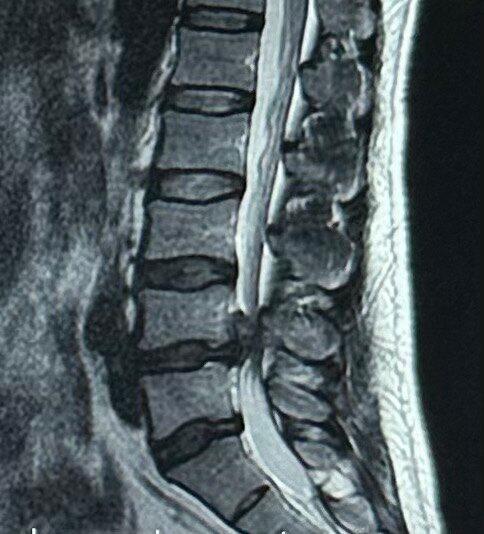

27岁腰椎间盘突出!一年时间治愈!作者:值友3948196981我确诊腰椎间盘突出是去年突然腿脚发麻走路困难,之后整夜疼的睡不着,但想着自己还年轻,就坚持保守治疗,经过自己不断的摸索,终于在折腾小一年的时间后,现在可以快步走路,轻松弯腰没感觉!虽然听起来好像很轻松,但整个过程是真的很艰难!因为自己经历过,就想...

腰椎间盘突出低龄化,运动不足是重要原因(人民日报健康客户端记者 高瑞瑞)“一到晚上就喊腰疼,开始我并没有在意,直到孩子告诉我他从腰、屁股到腿都疼,严重的时候睡不好觉,我们才着急,带着孩子去医院就诊,竟然被确诊腰椎间盘突出症,真担心。”一位学生的妈妈告诉人民日报健康客户端记者。腰椎间盘突出症是一种常见的...

╯﹏╰ 不少患者仅十几岁!警惕腰椎间盘突出症低龄化严重时甚至睡不好觉。家长这才着了急,带孩子去医院就诊,检查发现竟是得了腰椎间盘突出症。“以前只知道年纪大的人有这个病,哪能想到孩子也会得?”小乐的母亲王女士既痛悔又诧异。她咨询医生后才知道,小乐患上腰突症,很可能与他经常久坐、运动太少有关。“他平时不爱动,课...

警惕腰椎间盘突出症低龄化严重时甚至睡不好觉。家长这才着了急,带孩子去医院就诊,检查发现竟是得了腰椎间盘突出症。 “以前只知道年纪大的人有这个病,哪能想到孩子也会得?”小乐的母亲王女士既痛悔又诧异。她咨询医生后才知道,小乐患上腰突症,很可能与他经常久坐、运动太少有关。 记者采访发现,类似...

新华视点|不少患者仅十几岁 警惕腰椎间盘突出症低龄化严重时甚至睡不好觉。家长这才着了急,带孩子去医院就诊,检查发现竟是得了腰椎间盘突出症。 “以前只知道年纪大的人有这个病,哪能想到孩子也会得?”小乐的母亲王女士既痛悔又诧异。她咨询医生后才知道,小乐患上腰突症,很可能与他经常久坐、运动太少有关。“他平时不爱动,课...